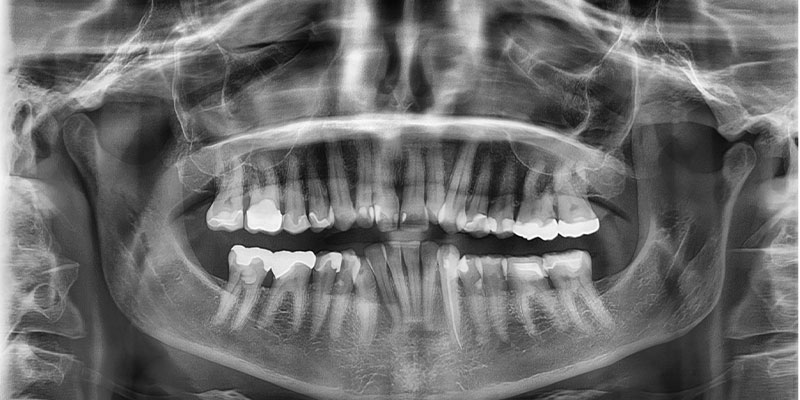

عکس opg؛ اشعه ایکس پانورامیک دندان که ارتوپانتوموگرام (OPT یا OPG) نیز نامیده می شود، یک عکس پانورامیک از تمام دندان ها است. این یک ابزار ضروری برای تشخیص و برنامه ریزی دندان است.

شما ممکن است با اشعه ایکس دندان آشنا باشید که در آن دندانپزشک یک تکه پلاستیک را در داخل دهان شما قرار می دهد تا آن را گاز بگیرید و چندین عکس می گیرد که یک یا چند دندان شما را نشان می دهد. این فقط یکی از انواع اشعه ایکس است. بسیاری دیگر نیز وجود دارد که یکی از آنها رادیوگرافی پانورامیک دندان است. این نوع اشعه ایکس کل دهان شما را در یک تصویر می گیرد. دریابید که اشعه ایکس پانورامیک دندان دقیقا چیست و چقدر می تواند مفید باشد

تصویربرداری OPG یک نوع از تصویربرداری رادیولوژیک است که به صورت پانورامیک از تمام دهان، دندانها و ساختارهای فک پایین و بالا تهیه میشود. این نوع تصویر، تصویری شبیه به نمای کلی و افقی از دندانها و فکها به پزشک میدهد و به او این امکان را میدهد که به راحتی مشکلات دندانها، پوسیدگیها، عفونتها، بیماریهای لثهای و مشکلات دیگر را شناسایی کند.

اشعه ایکس پانورامیک با این واقعیت مشخص می شود که دو فک بالا و پایین با تمام دندان ها، ریشه ها و همچنین حفره های سینوسی و مفصل گیجگاهی فکی برجسته می شوند.

ارتوپانتوموگرام پانورامیک دندان نیز نامیده می شود. این یک عمل رادیولوژی است که به دست آوردن تصویر بسیار گسترده ای از دندان را ممکن می کند:

دو ردیف دندان؛

استخوان های فک بالا و پایین؛

و همچنین استخوان فک بالا و فک پایین.

ارتوپانتوموگرام دقیقتر و کاملتر از معاینه دندانپزشکی بالینی، ضایعات دندانها یا لثهها را که نامرئی یا به سختی با چشم غیرمسلح قابل مشاهده هستند، مانند شروع حفرهها، کیستها، تومورها یا آبسهها را ممکن میسازد.

پانورامیک دندان همچنین ناهنجاری های دندان عقل یا دندان های نهفته را برجسته می کند.

رادیوگرافی دندان نیز برای اطلاع از موقعیت دندان ها و تکامل آنها به ویژه در کودکان استفاده می شود. در نهایت، نظارت بر تحلیل استخوان و وضعیت لثه ها را ممکن می سازد.

اشعه ایکس دندان یا ارتوپانتوموگرافی، این امکان را فراهم می کند که یک نمای پانوراما از دو قوس دندانی بیمار گرفته شود و در نتیجه وضعیت تمام دندان های او را تجسم کنید. با چنین پانورامیک دندانی یا ارتوپانتوموگرام، متخصص دهان و دندان می تواند به راحتی ناحیه مشکل را تشخیص دهد و اولین تشخیص اولیه را انجام دهد. اگرچه همه چیز در این عکس ها قابل مشاهده نیست، اما با این وجود، هم در زمینه تشخیص مشکلات و هم در زمینه پیشگیری، کمک بزرگی به دندان پزشکان می کند.